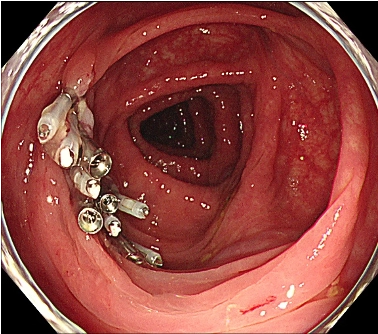

図4: 切除後の創部をクリップで閉鎖(サンプル)

図4. 切除後の創部は、出血の予防策として内視鏡的にクリップで閉鎖します。